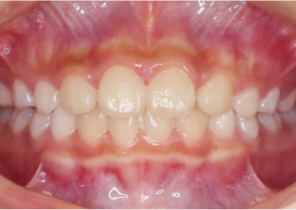

Opis przypadku nr 2

7 lat, 11 miesięcy, 24 etapy leczenia Invisalign® Palatal Expanders

Dzięki uprzejmości dr. Davida R. Boschkena

Przed ekspansją eInvisalign Palatal Expander

Po ekspansji Invisalign Palatal Expander

Po leczenie Invisalign Palatal Expander